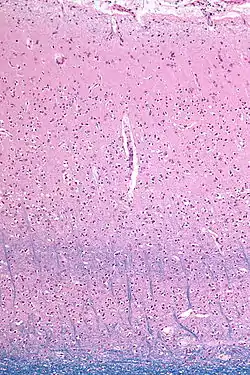

![]() Micrograph showing the visual cortex (predominantly pink). The blue, horizontal band in the lower half of the image are the bands of Baillarger/the line of Gennari. Subcortical white matter (predominantly blue) is seen at the very bottom of the image. HE-LFB stain. | |